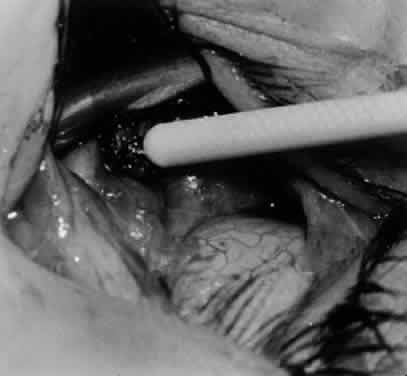

Fig. 24. The eyelid speculum is removed and a Desmarres lid retractor is placed inferiorly. The inferior oblique muscle is drawn superiorly and nasally. The fusiform expansion of the inferior oblique muscle is evident on the posterior border, where the nerve to the inferior oblique muscle and artery and vein enter the inferior oblique muscle. The Stevens muscle hook is used to hook the neurovascular bundle.

Fig. 25. The hook is advanced further for identification of the neurovascular bundle on the inferior oblique muscle.